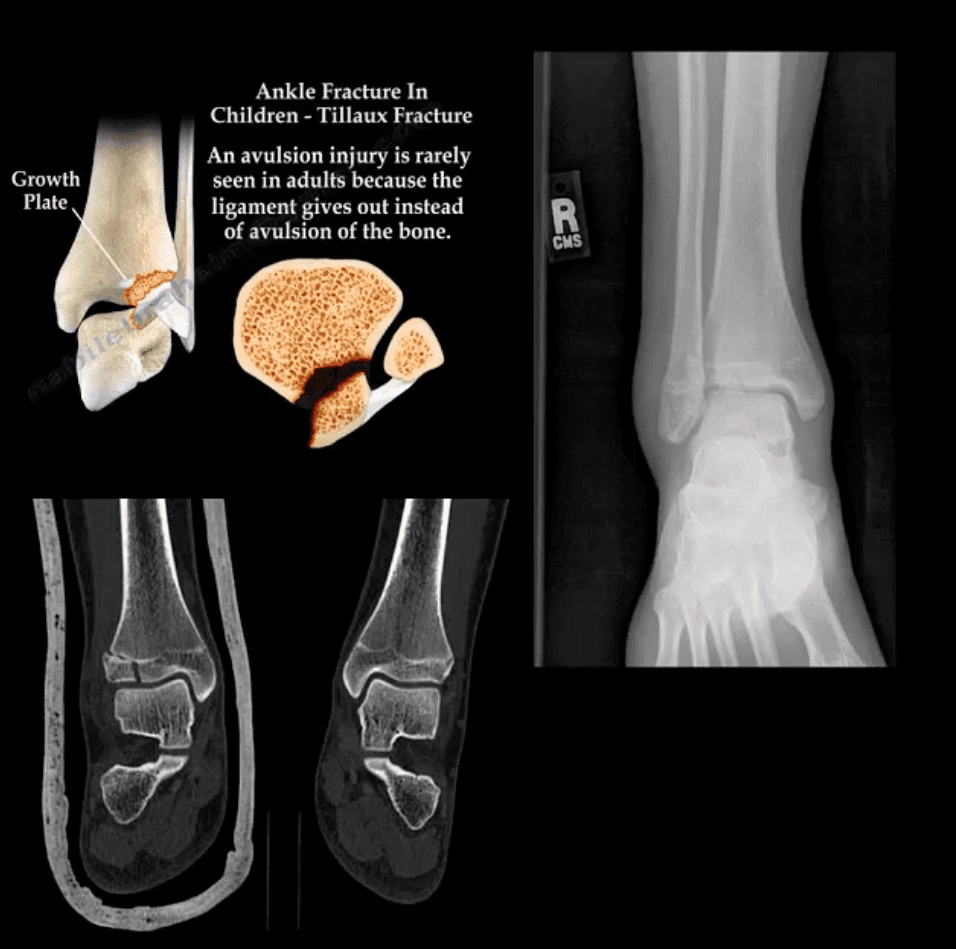

Tillaux Fx

- Pediatric Fx affecting older child when medial side of the physis is closed or about to close with lateral side till open. Avulsion by anterior tibi-fibular ligament. Complications: 2nd dry/premature OA. Rx: can be conservative if stable by boot cast immobilization.

Pediatric Growth Plate Injuries

- Salter-Harris classification helps to diagnose and prognosticate physeal injuries.

- Helpful mnemonic: SALTR

- S: type 1-slip through growth plate

- A: type 2-above, Fx extends into metaphysis

- L: type 3-lower, intra-articular Fx extends through the epiphysis

- T: type4, “through” Fx extends through all: physis, metapysis and epiphysis.

- R: type 5, “ruined.” Crush injury to physis leading to complete death of teh growth plate

- Type 1 and 5: present with no fracture

- Type 2: has the best prognosis and considered the most common.

- Management: referral to pediatric orthopedic surgeon

- Complications: early physis closure, limb shortening, premature OA and others.